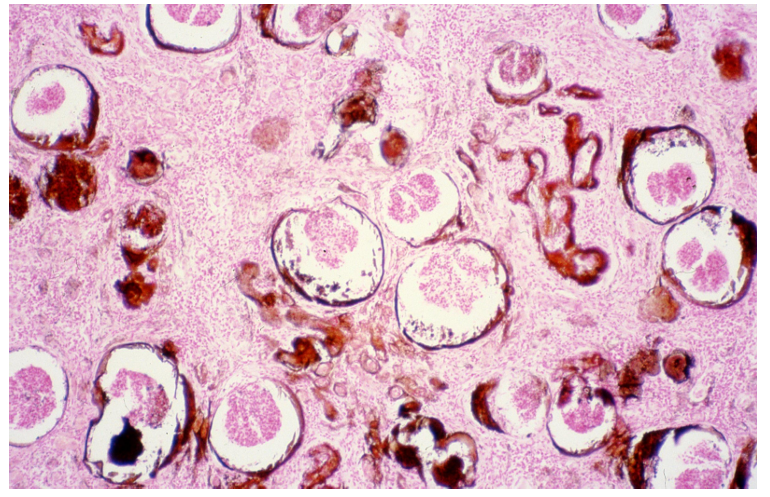

Pneumonia TBC miliaris - poultry

Description: Pathological content fills lung fistulas. It is formed by round foci with central necrosis surrounded by specific granulation tissue. Close to necrotic parts of granuloma it is predominated by macrophages (epithelioid cells) and lymphocytes, which are numerous at the periphery. Start of giant cell formation can be observed in some granulomas.

Etiology: Caused by mycobacterium avium which is transmitted by ingestion or inhalation.

Pathogenesis: Basic form is the tubercle which appears as a pin-head sized focus on tissue. Large masses arise by coalescence of smaller tubercles. Bacteria can spread to lymph nodes and other organs by lymphatic system and bloodstream. Generalization may be sudden and massive if large numbers of bacilli enter the bloodstream.

this is?

Pneumonia TBC miliaris- poultry (ZN) same as nr. 263

Ziehl-Nielsen staining is used for special proof of mycobacterium. Positive acid-fast rods bacilli and their clumps of red color are mainly found in the necrotic center. During the generalized TBC process, the lungs are the last organ with dissemination of tubercles.